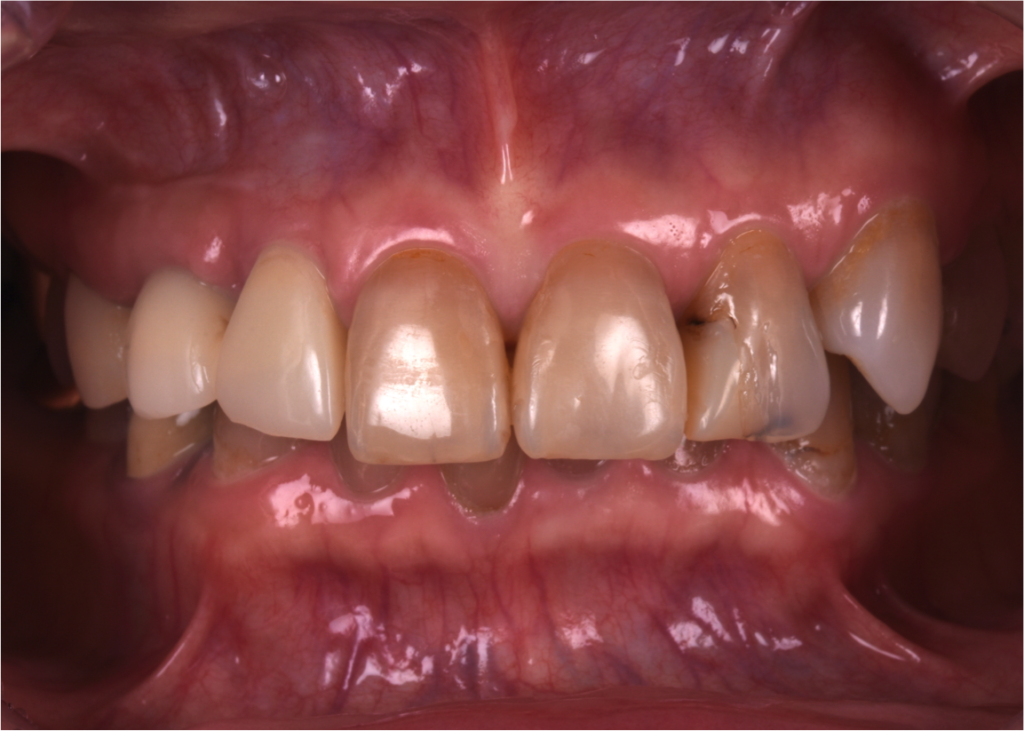

昔のコンポジットレジンの変色と2次カリエス(過去の治療の再発)

過去に上の前歯の複数歯に対してコンポジットレジンが充填されており、その部分が経年的に変色しています。また、詰め物の内部が黒くなっており、2次カリエス(むし歯の再発)にもなっています。